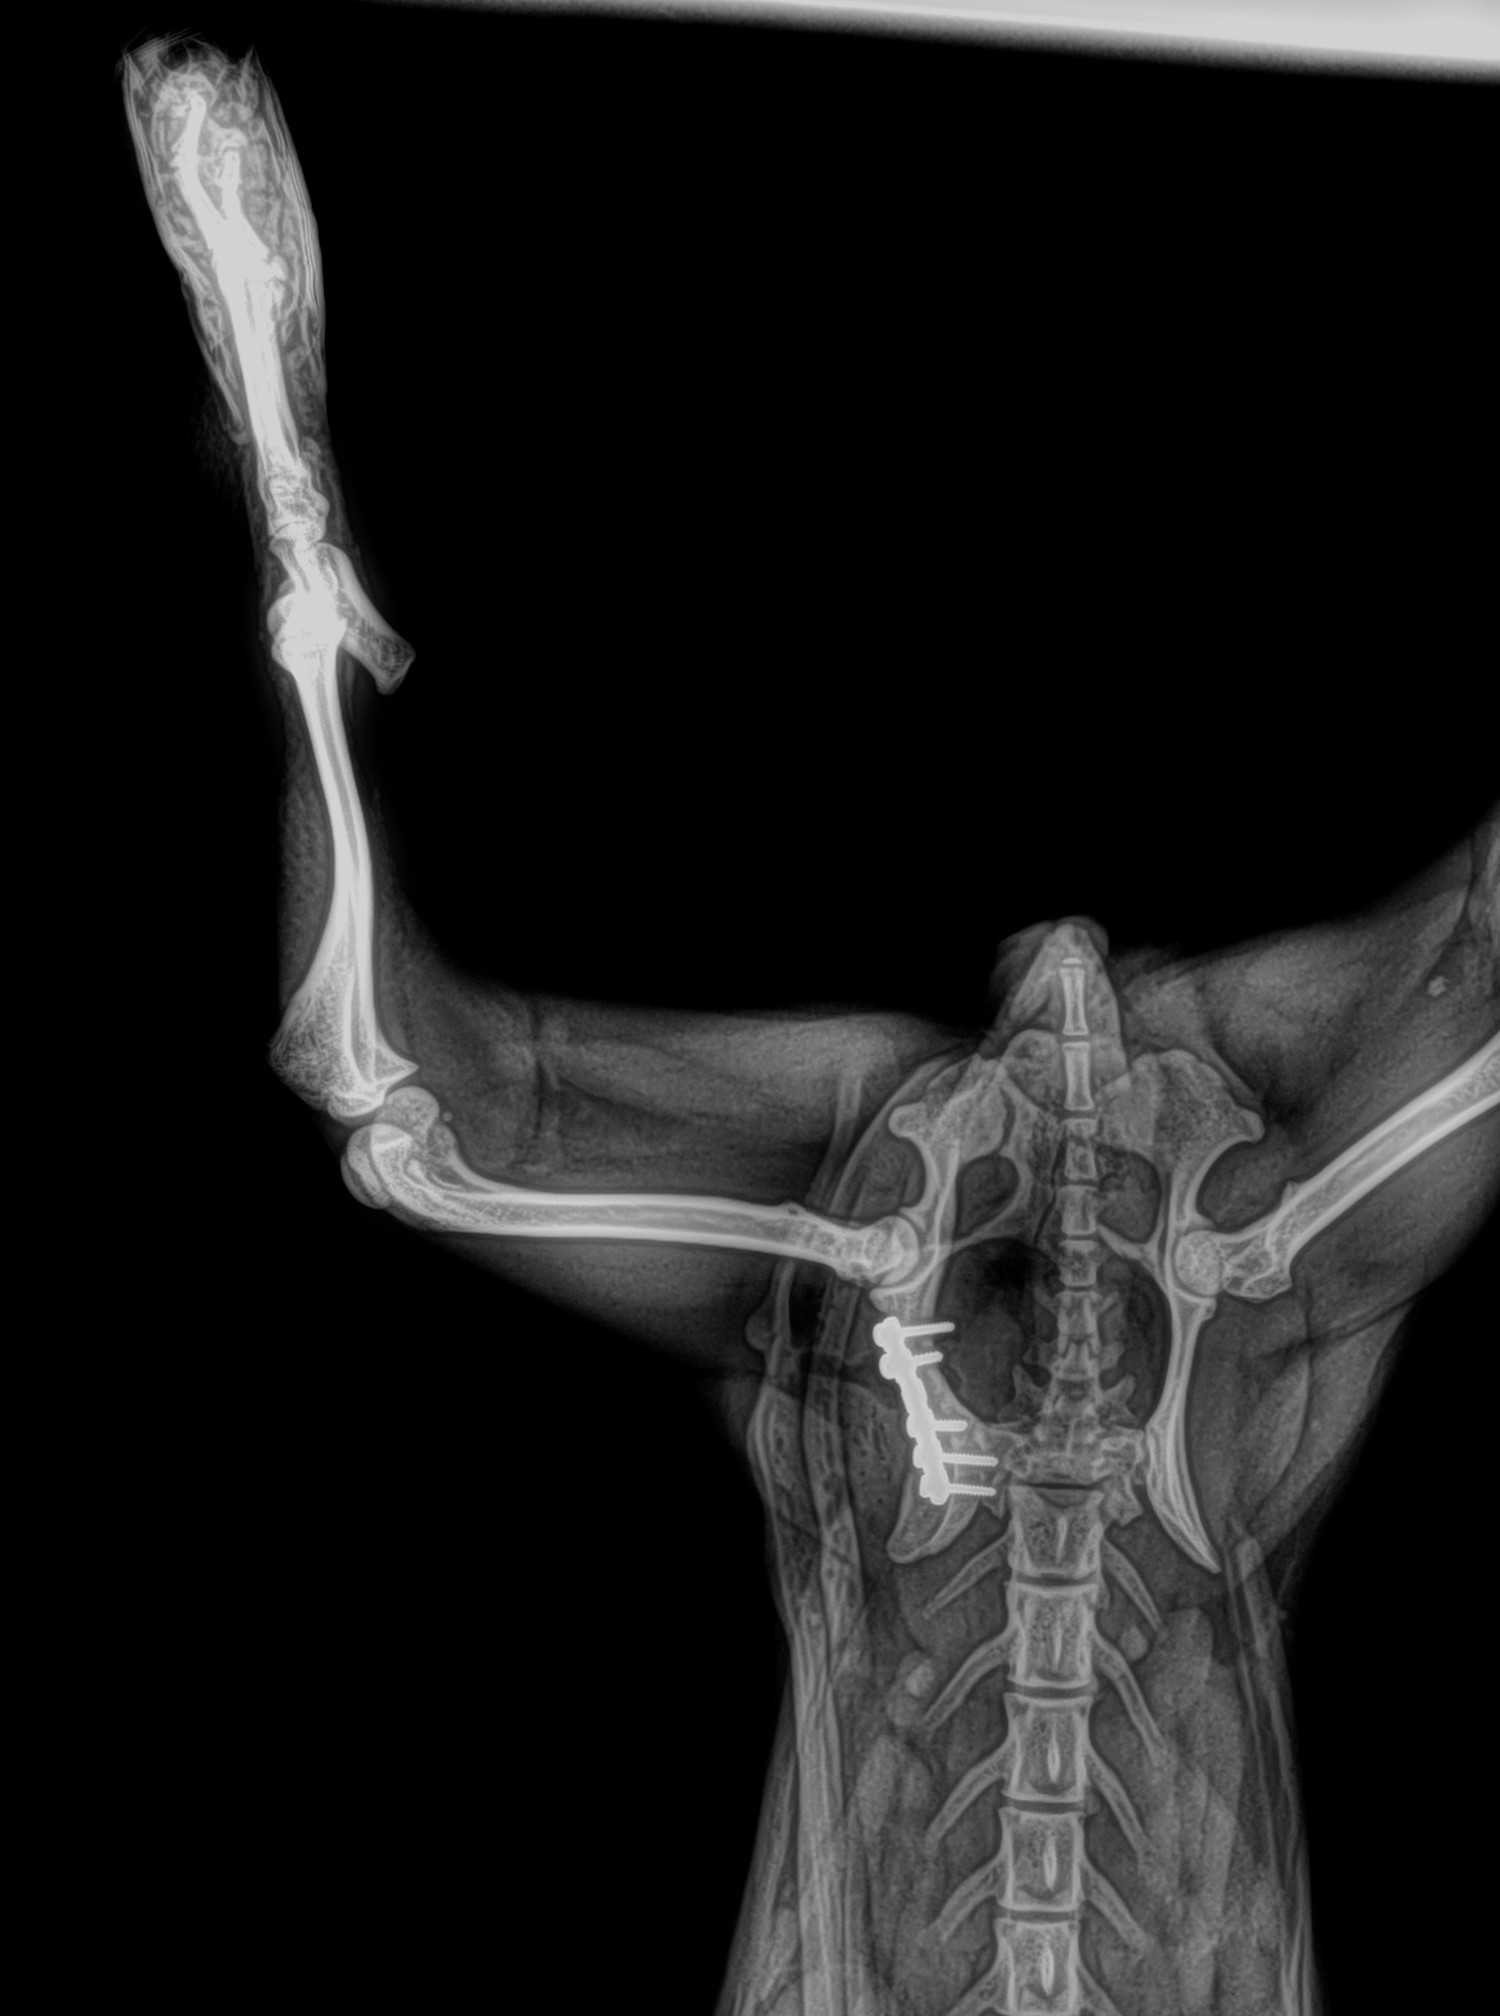

Radiología Digital como Herramienta Complementaria en el Dictamen de Bienes Muebles

Desde el descubrimiento de los rayos “X” y las placas radiográficas por Wilhelm Conrad Roentgen y su posterior difusión a través de la Asociación Físico médica de Wurzburg el 28 de diciembre de 1895, que fue la primera asociación que habló de los nuevos rayos que podían penetrar el cuerpo y fotografiar los huesos, ha habido muchos cambios tanto en la forma de obtener, procesar e incluso en la forma de visualizar, manejar y almacenar las placas radiográficas.